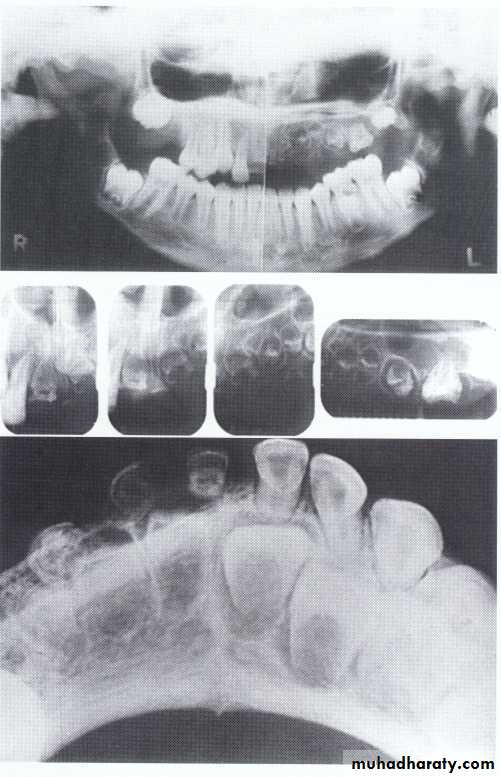

Dentin dysplasia, type II. panoramic &periapical films of the same case show obliteration of the pulp chamber, reduction in the caliber of root canals, and pulp stones obscuring the flame-shaped pulp chambers.

Periapical inflammatory lesions are associated with some of the mandibular anterior teeth.